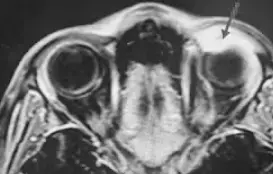

По заключению КТ глазницы с внутривенным болюсным контрастированием в верхне-медиальном отделе правой орбиты определяется объемное образование 2,8×1,9×1,1 см с четкими и ровными контурами, жидкостной плотностью до 15 HU, не накапливает контрастный препарат.

На МРТ видно, что новообразование состоит из двух частей, одна из которых кистовидная, а другая гипоэхогенна по отношению к мозговой ткани. Образование вызывает компрессию мышц глаза, смещает зрительный нерв.